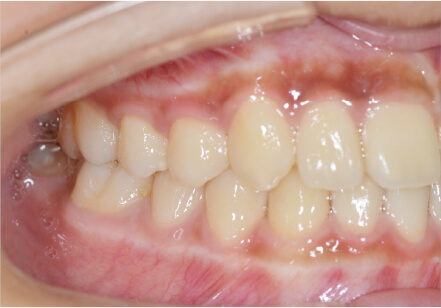

叢生の症例

19歳

/

女性

相談内容

上の前歯が出っ歯、下の前歯がガタガタ

カウンセリング・診断結果

抜歯承諾、IPR承諾、アタッチメント承諾、ミニインプラント承諾、アレルギー有・叢生(凸凹)

治療内容・方法

全顎アライナー矯正 抜歯予定だったが抜歯リスク高いため抜歯なしでIPR量を増やす

術後の経過・現在の様子

クリアライナー

治療のリスク

痛み・歯根吸収・歯肉退縮・虫歯・後戻り

費用・治療期間

880,000円、1年5ヶ月

トレーニングなど